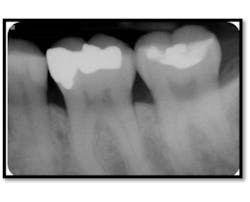

Probing depths posterior and anterior teeth 3-4mm

Note the bone fill on the vertical defects of #8-9 and 18 and 19

The furcation involvement in both molars has resolved